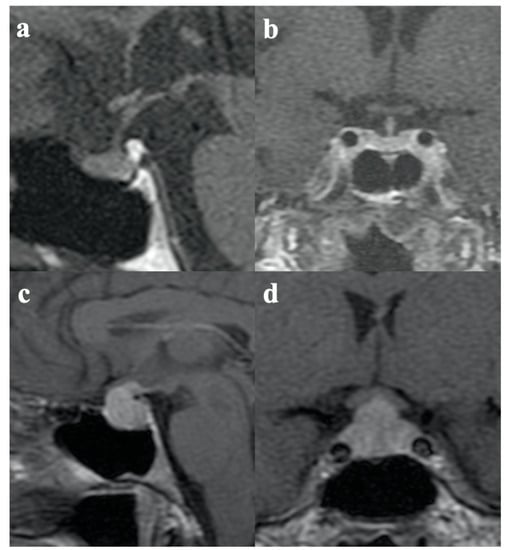

- Adenohypophysitis (AH) in cases with involvement of the anterior pituitary (pituitary enlargement) and without signs of involvement of the posterior pituitary.

- Infundibulo-neurohypophysitis (INH) in cases with signs of infundibulum, pituitary stalk, and posterior pituitary involvement (thickness of the pituitary stalk and absence of the posterior pituitary bright spot on T1w images) without involvement of the adeno-pituitary.

- Panhypophysitis (PH) in cases with involvement of the anterior pituitary, posterior pituitary, pituitary stalk, and infundibulum.

- Tartaglione, T.; Chiloiro, S.; Laino, M.E.; Giampietro, A.; Gaudino, S.; Zoli, A.; Bianchi, A.; Pontecorvi, A.; Colosimo, C.; De Marinis, L. Neuro-radiological features can predict hypopituitarism in primary autoimmune hypophysitis. Pituitary 2018, 21, 414–424. [Google Scholar] [CrossRef]

- Chiloiro, S.; Tartaglione, T.; Angelini, F.; Bianchi, A.; Arena, V.; Giampietro, A.; Mormando, M.; Sciandra, M.; Laino, M.E.; De Marinis, L. An Overview of Diagnosis of Primary Autoimmune Hypophysitis in a Prospective Single-Center Experience. Neuroendocrinology 2017, 104, 280–290. [Google Scholar] [CrossRef] [PubMed]